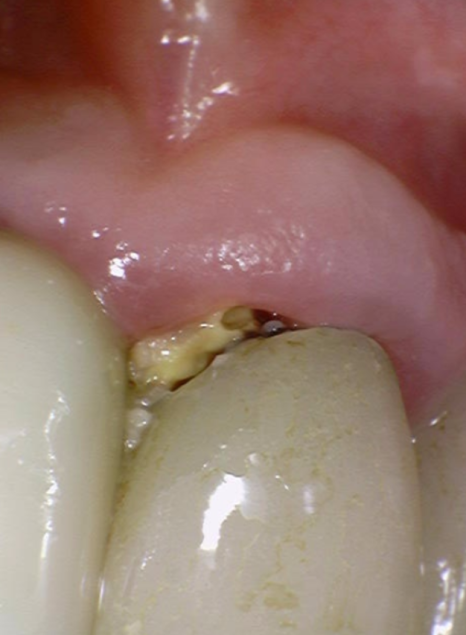

정확한 확인을 위해 기구(탐침)로

조심스럽게 건드려 보았더니,

단단해야 할 치아가 삭아 '쑥!' 하고

기구가 들어가 버렸습니다.

충치가 아주 깊다는 증거였죠.

기존 브릿지를 제거하고

내부 상태를 확인했습니다.

예상대로 음식물 찌꺼기와 오염이 심각했지만,

여기서 불행 중 천만다행인 사실...

230516

남은 치아의 양이 적당하여

발치는 피할 수 있는 상황이었어요.